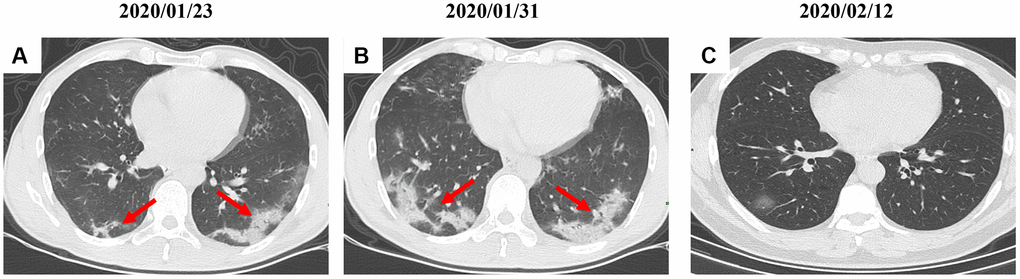

By Mar 23, 2020, 60 (60/66, 91%) patients had been discharged. 6 (6/66, 9%) patients were still in hospital, and two patients had died because of ARDS. Patient 1, 78-year-old man with hypertension, who died on day 15 after admission (Figure 1B). Patient 2, 47-year-old man with type 2 diabetes, whose CT scan presented rapid radiology progression (Figure 3A, 3B). The radiological change of COVID-19 pneumonia develops fast during the first seven days (Figure 3C, 3D). Some of patch lesion could be absorbed and change into reticular spline lesion (Figure 4A, 4B). Meanwhile, some patients achieved rapid recovery with significant improvement of CT sign (Figure 4C, 4D) and clinical symptoms. We also did some CT follow-up scans for few patients, which showed the aggravated progression of disease since admission and rapid recovery after treatment (Figures 5 and 6). Disappearance of lesions and significant improvement of clinical symptoms were observed in two patients (Figure 5: a 54-year-old male patient; Figure 6: a 54-year-old female patient).

Figure 6. A serial CT images after admission of a 54-year-old female patient. (A) Patch ground-glass opacity mainly located in the left lower lobe. (B) Significant larger patch ground-glass opacities were observed in both lower lobes after 8 days. (C) Follow-up CT scans on day 20 after admission show a remarkable improvement. Typical lesions were marked with red arrows.